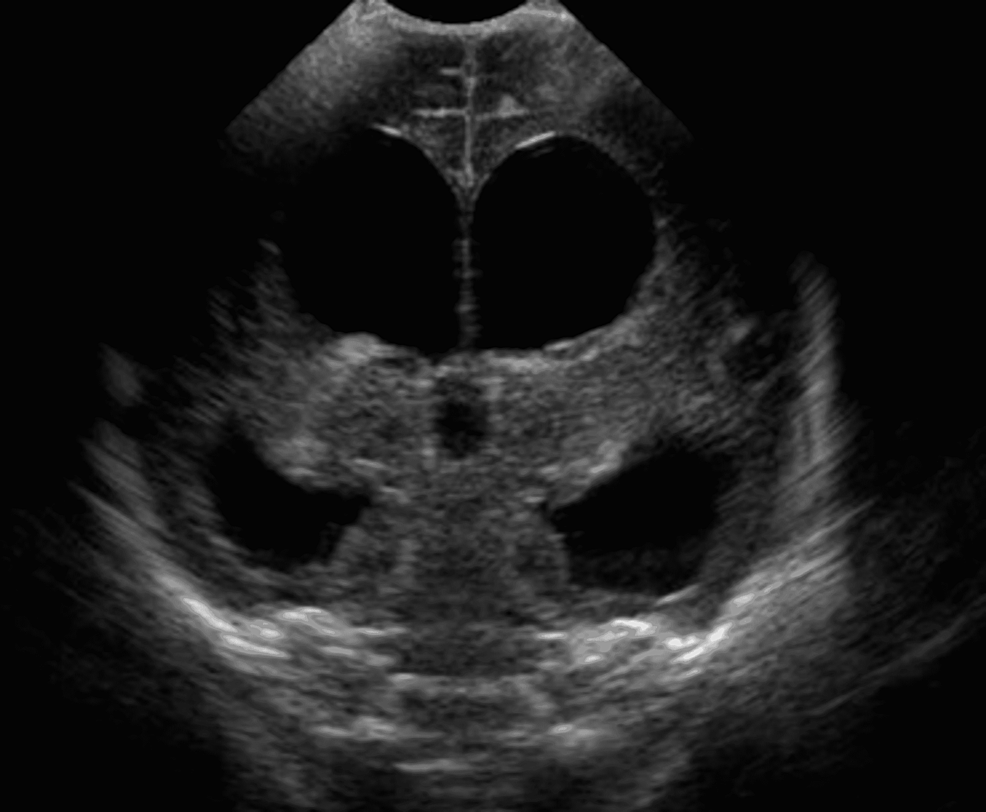

Neurosonogram is a detailed ultrasound examination of the fetal brain and central nervous system. It is usually performed when there is suspicion of brain abnormality or in high-risk pregnancies.

It is usually performed between 18–24 weeks of pregnancy, but can be done later if required.